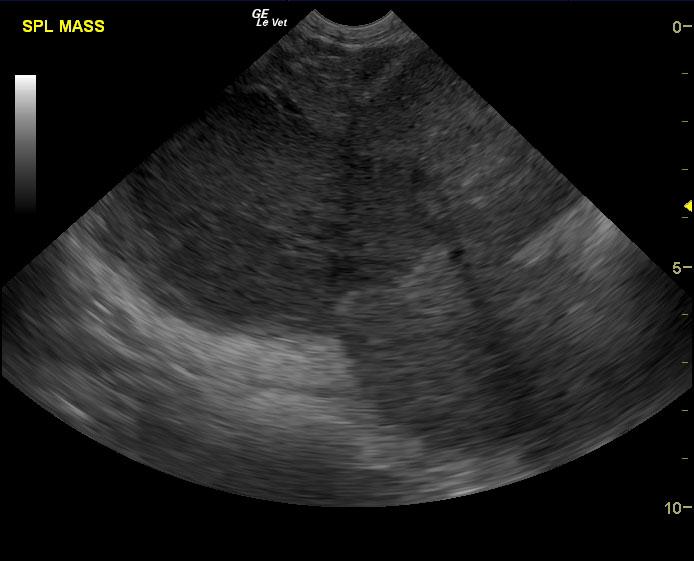

A 7 year old intact male pit bull terrier was presented for an abdominal tumor. Abnormalities on CBC and serum biochemistry were severe anemia and hypoalbuminemia.

A 7 year old intact male pit bull terrier was presented for an abdominal tumor. Abnormalities on CBC and serum biochemistry were severe anemia and hypoalbuminemia.